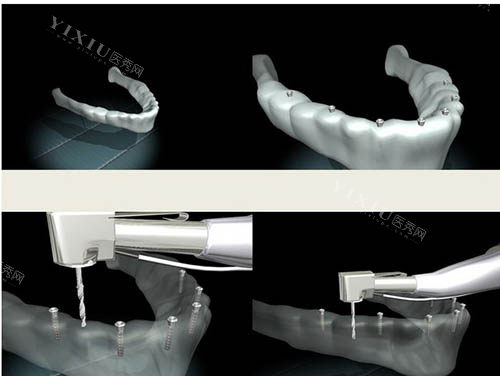

手术风险与改善能力:

老年人身体机能下降,免疫力较弱,手术耐受性降低,可能引发出血、感染等并发症。

术后改善周期较长,需严格护理口腔卫生,但部分患者因行动不便或认知功能下降,难以完成护理要求。